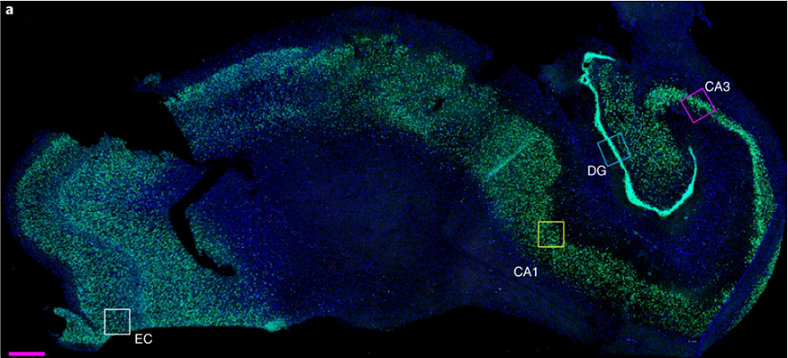

人腦海馬體切片(圖片來源:E. P. Moreno-Jimenez et al., 2019)